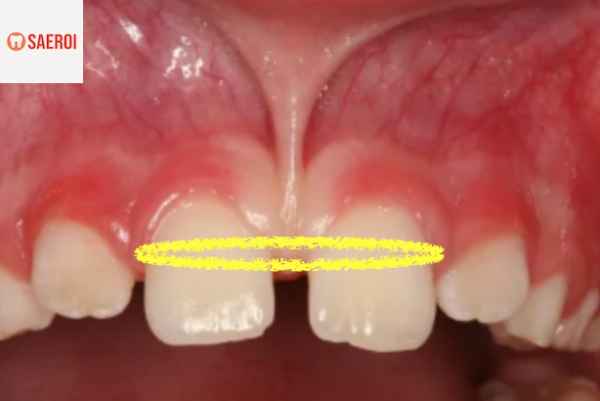

아래 두 사진은

셀프 교정을 시행하고 나타난

부작용들입니다.

벌어진 앞니를 교정하기 위해

고무줄을 양쪽에 끼웠다가

고무줄이 잇몸을 파고들어

잇몸 조직이 파괴된 케이스입니다.

잇몸 지지 조직이 무너져

치아가 돌출된듯한 모습을 하고있습니다.